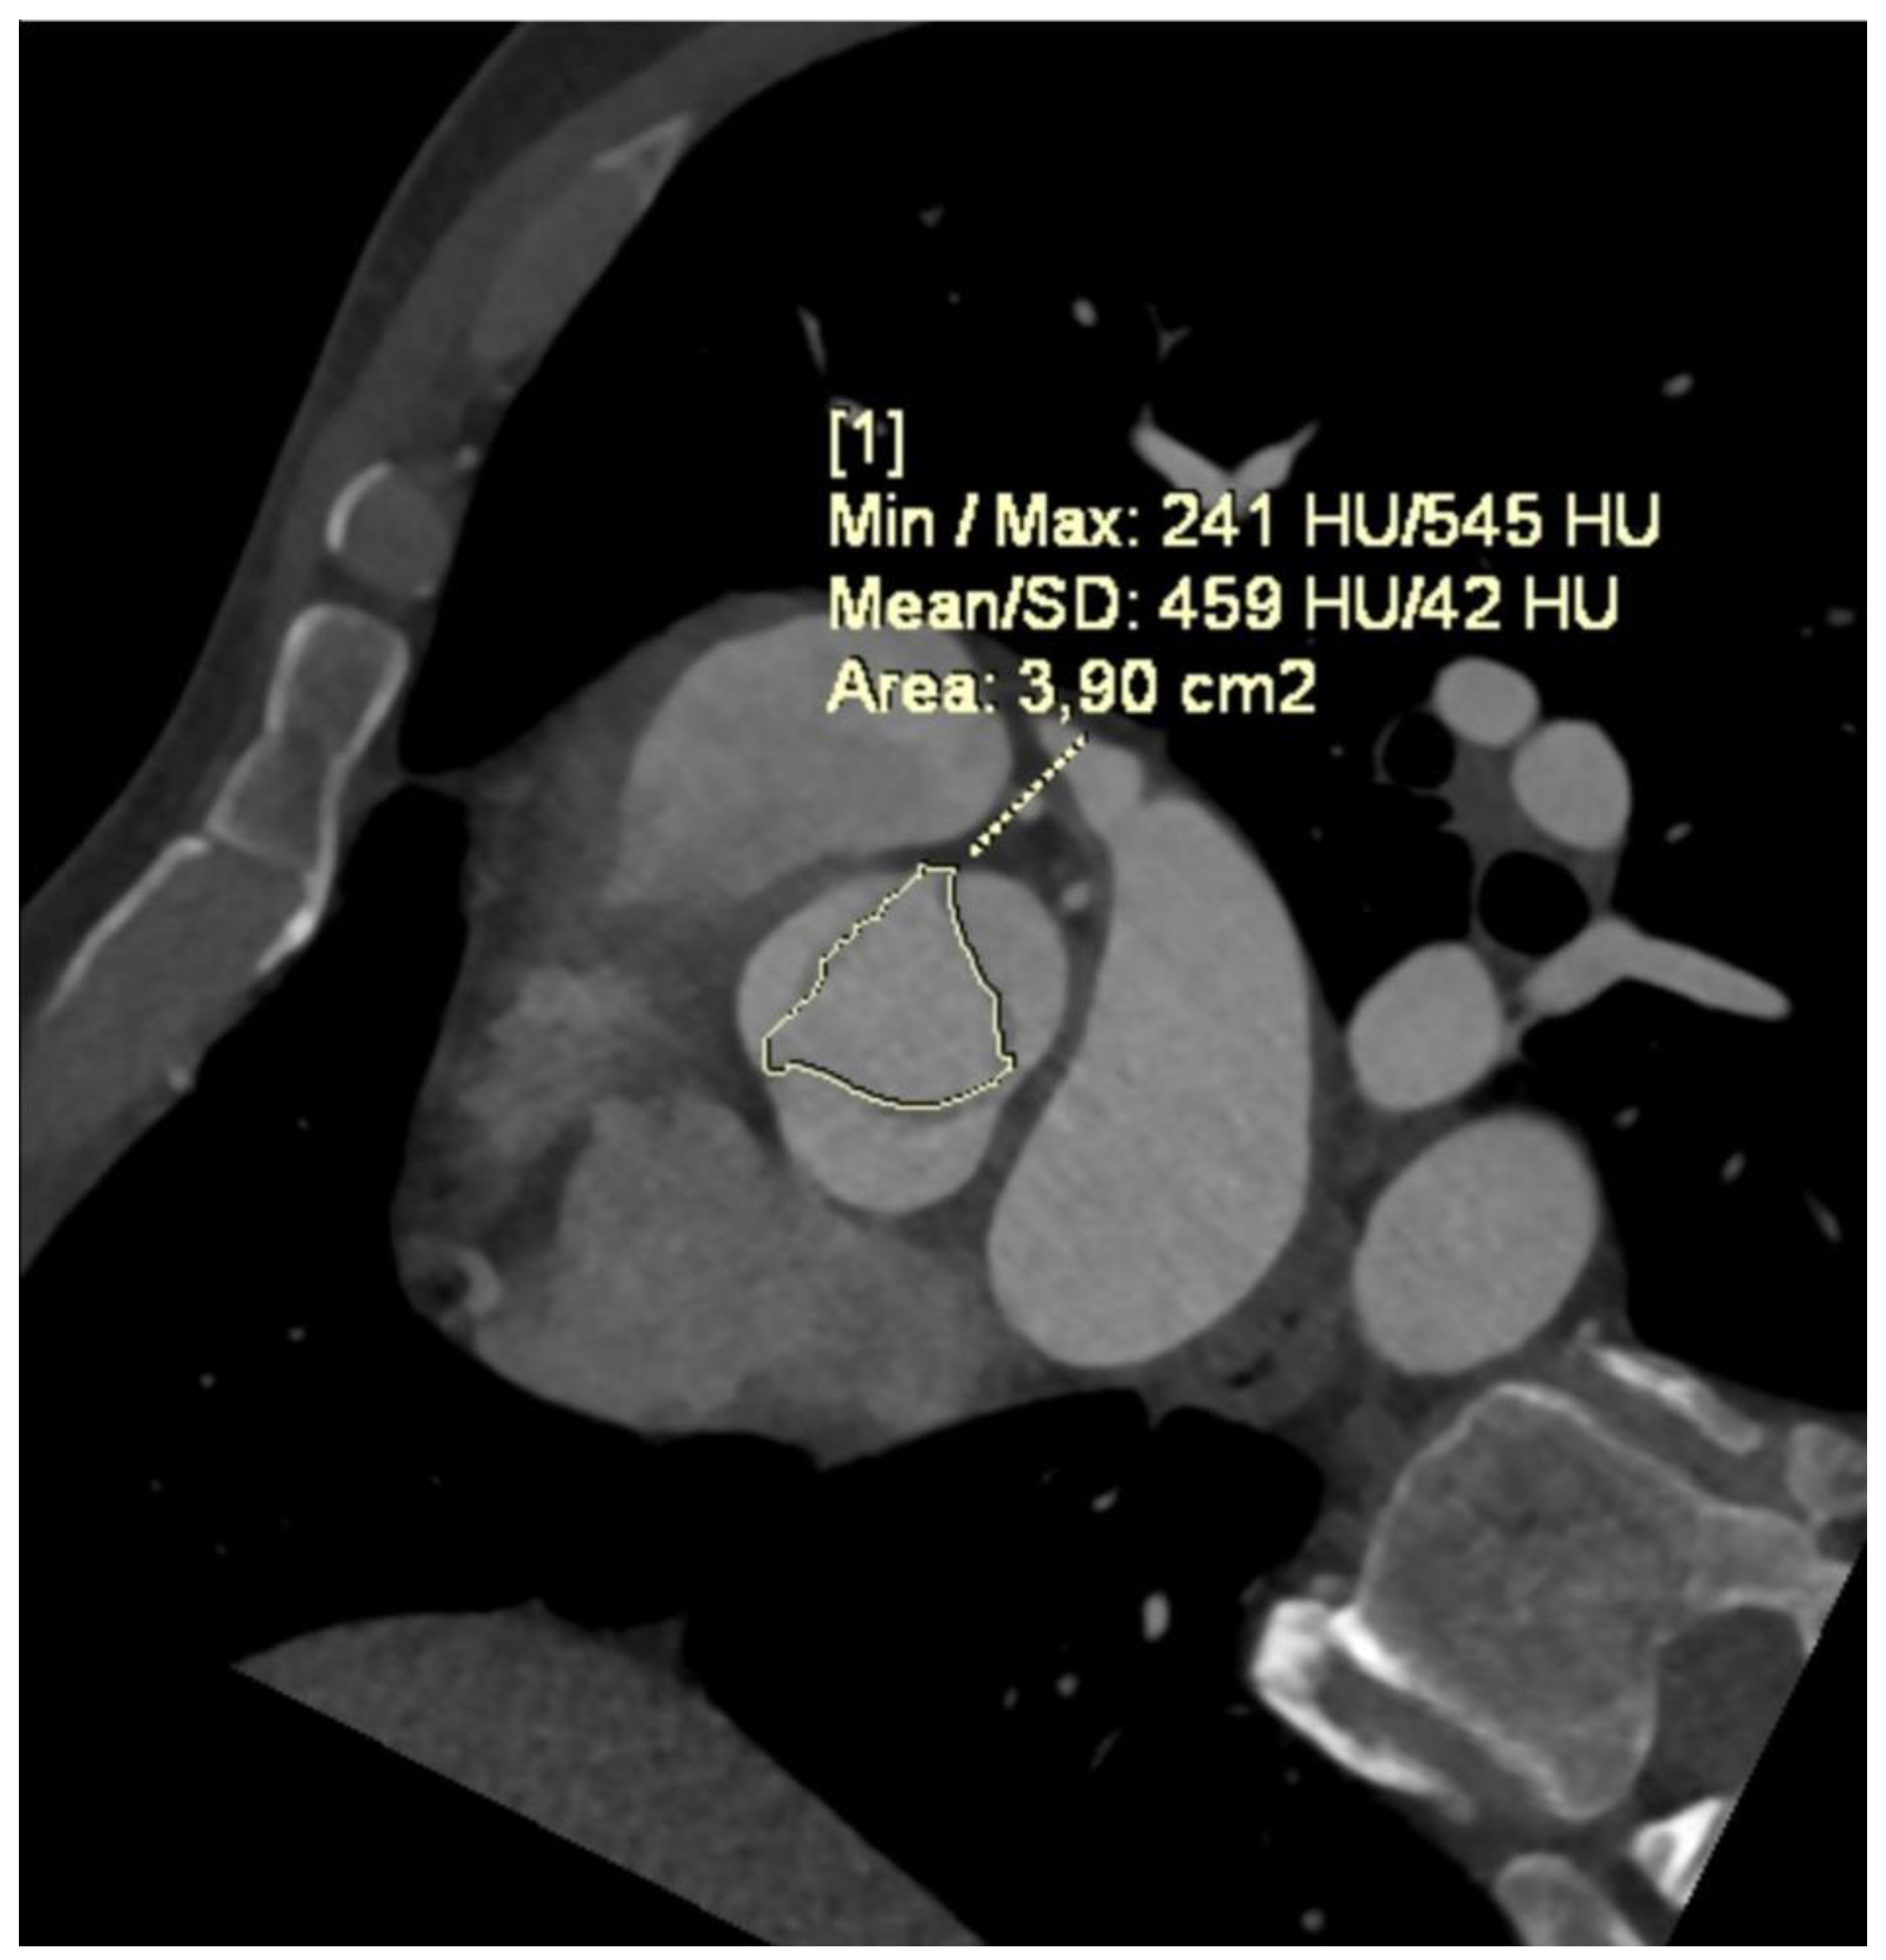

- Pandey, N.N.; Sharma, S.; Jagia, P.; Gulati, G.S.; Kumar, S. Feasibility and Accuracy of Aortic Valve Calcium Quantification on Computed Tomographic Angiography in Aortic Stenosis. Ann. Thorac. Surg. 2020, 110, 537–544. [Google Scholar] [CrossRef] [PubMed]